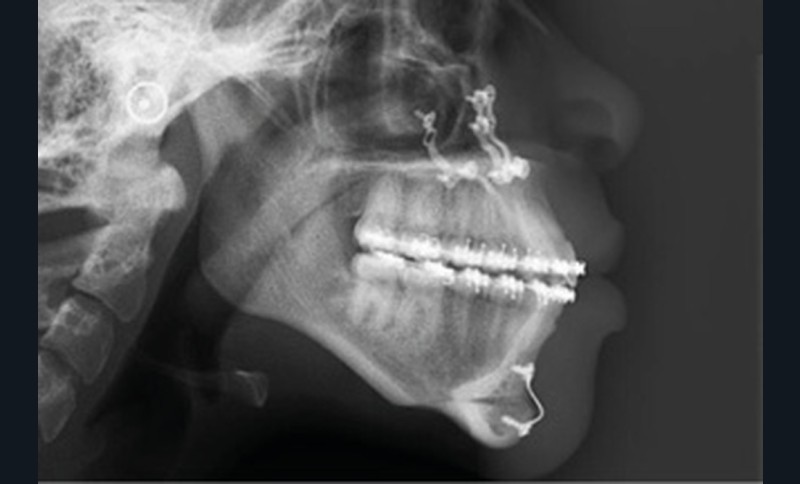

L’examen radiologique se compose d’un orthopantomogramme montrant les troisièmes molaires et des condyles symétriques, d’une téléradiographie de profil objectivant des voies aériennes supérieures libres, et d’une radiographie du poignet (stade de croissance selon Greulich et Pyle : CS6 = fin de croissance).

L’analyse céphalométrique de Tweed met en évidence les valeurs suivantes : FMA 37° (typologie hyperdivergente), SNA 89°, SNB 90°, ANB -1° et AoBo -6 mm (classe III squelettique), I/F 112° (vestibulo-version incisive maxillaire) et IMPA 84° (linguo-version incisive mandibulaire) : compensations de classe III.

L’analyse de Ricketts conclut à une classe I squelettique sur un schéma méso tendance dolichofacial avec une vestibulo-position de l’incisive mandibulaire.

Selon Sassouni, Anisa est rétro-archiale, en classe III squelettique de 9 mm et alvéolaire de 12 mm avec une incisive maxillaire en vestibulo-position de 6 mm.